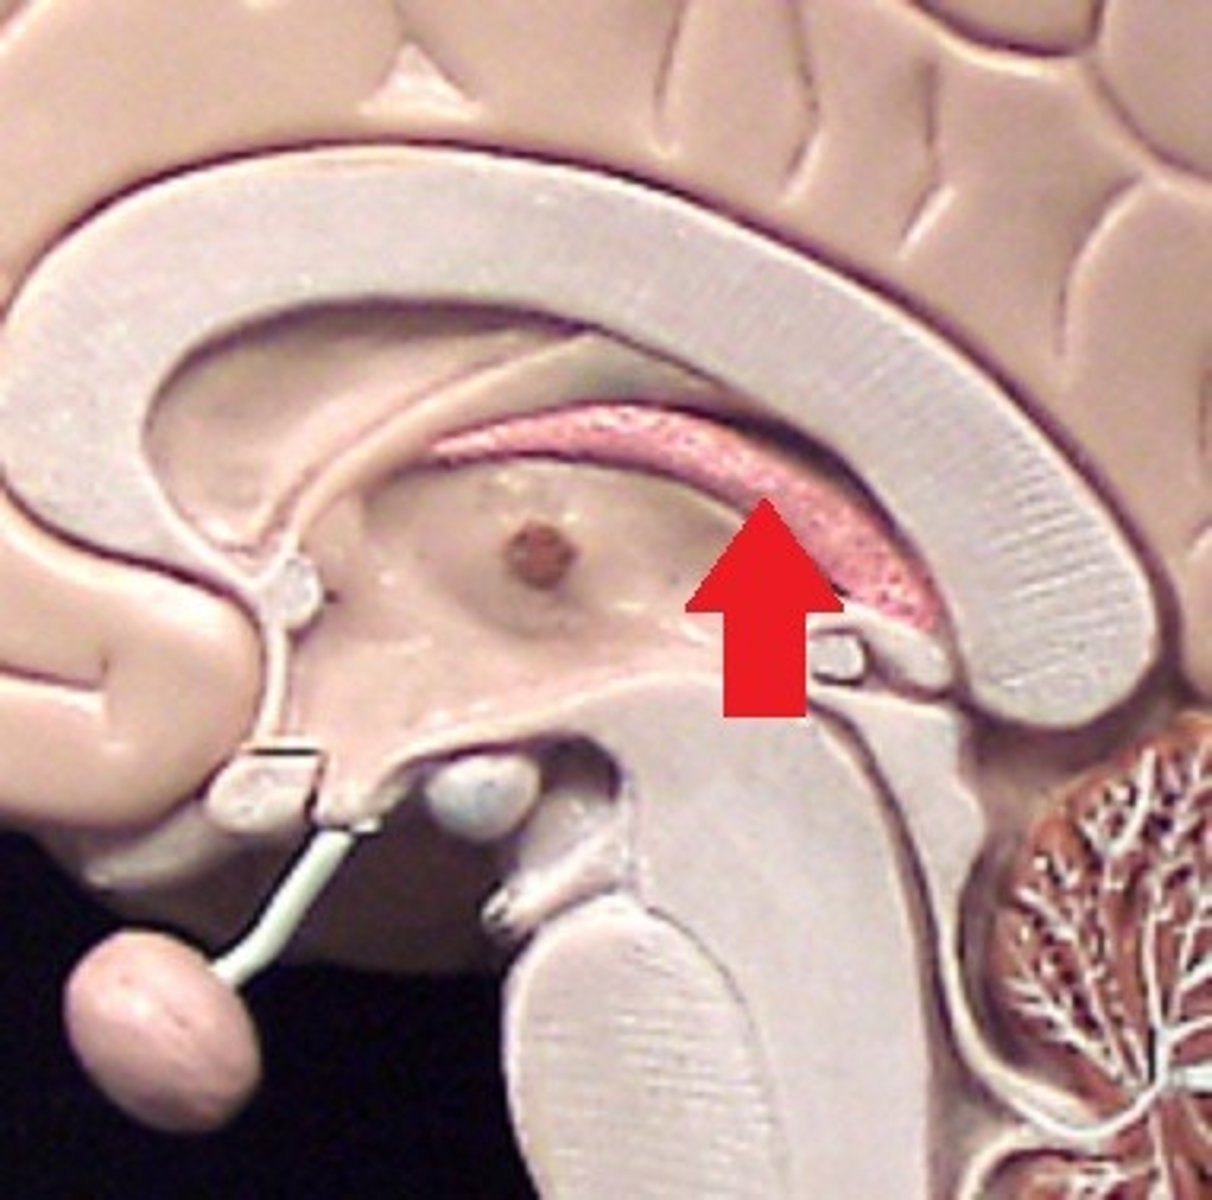

Corpus callosum

Fornix

Septum pellucidum

Intermediate mass of the thalamus

Thalamus

Hypothalamus